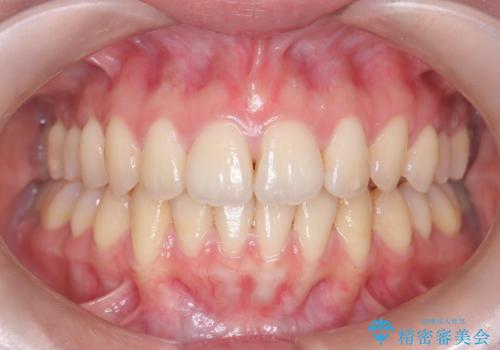

- 前歯の突出を主訴に来院されました。

アンカースクリューとインビザラインを用いて遠心移動を行うことでできる限り前歯を下げて叢生の改善を行いました。